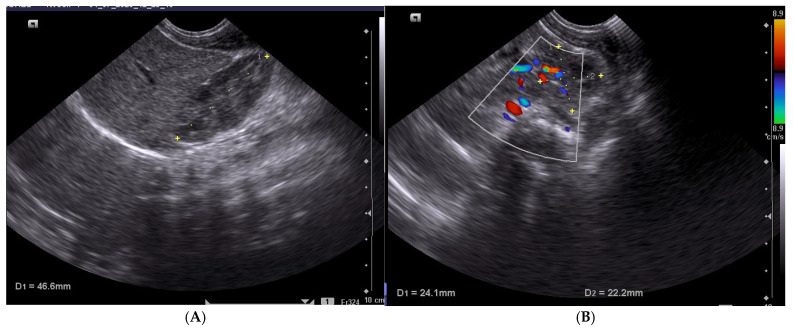

Methods: A prospective study was conducted at Polizu Maternity, Bucharest, Romania, involving a cohort of 100 term newborns with a gestational age (GA) between 37 and 42 weeks, all delivered at the INSMC "Alessandrescu-Rusescu" Polizu Maternity Hospital. Routine renal ultrasound was performed for all term newborns within the first 72 h of life. Renal dimensions were measured in the longitudinal and axial sections, and the volume was calculated.

Results: The average kidney dimensions were as follows: length 42.0 ± 3.4 mm, width 22.6 ± 2.6 mm, and thickness 19.9 ± 2.5 mm. Renal volume ranged from 5.1 to 18.9 mL, with an average of 10.2 ± 2.5 mL. The kidney volume was significantly correlated with gestational age (r = 0.195; p = 0.05) and birth length (r = 0.267; p = 0.008), and most strongly with birth weight (r = 0.306; p = 0.002).